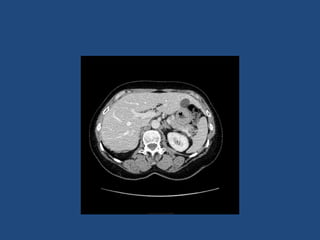

• CT better at eliminating malignancy

(dedicated CT looking at Hounsfield units (HU)

and washout characteristics)

– <10HU = benign (sens 71%, spec 100%)

• MRI may characterise phaeos better

• FDG-PET good for phaeos and cancer

• FNA – consider if cancer history and >10HU on CT

after exclusion of phaeo

Imaging

•

>6cm high suspicion of malignancy

3-6cm repeat imaging in 3-6M

Delayed washout on contrast is suggestive

most are often inhomogeneous, irregular

margins

• Look for invasion of IVC

• Always do CAP and consider bone scan and

pet if in doubt

• Don’t ever biopsy (tumour spill)